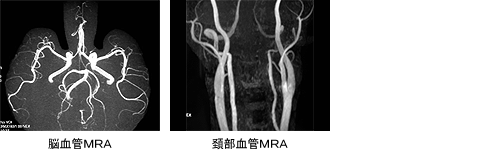

◆MRA検査

MRI 装置を使用した血管撮影(MR Angiography)のことで、造影剤や薬を使わずに脳や頚の血管を写す検査です。脳動脈瘤や血管の細い部分などを発見できます。検査の受け方はMRI と同じで、仰向けに横になって頂いて検査をします。